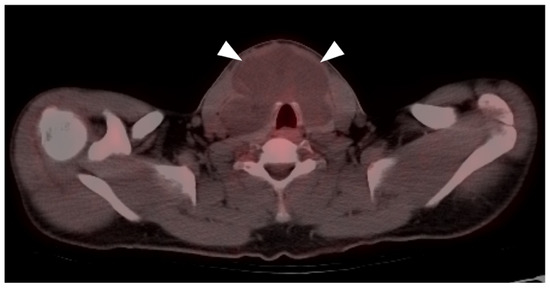

- Murphy, G.; Hussey, D.; Metser, U. Non-cutaneous melanoma: Is there a role for18F-FDG PET-CT? Br. J. Radiol. 2014, 87, 20140324. [Google Scholar] [CrossRef] [Green Version]

- Falch, C.; Mueller, S.; Kirschniak, A.; Braun, M.; Koenigsrainer, A.; Klumpp, B. Anorectal malignant melanoma: Curative abdominoperineal resection: Patient selection with 18F-FDG-PET/CT. World J. Surg. Oncol. 2016, 14, 185. [Google Scholar] [CrossRef] [Green Version]